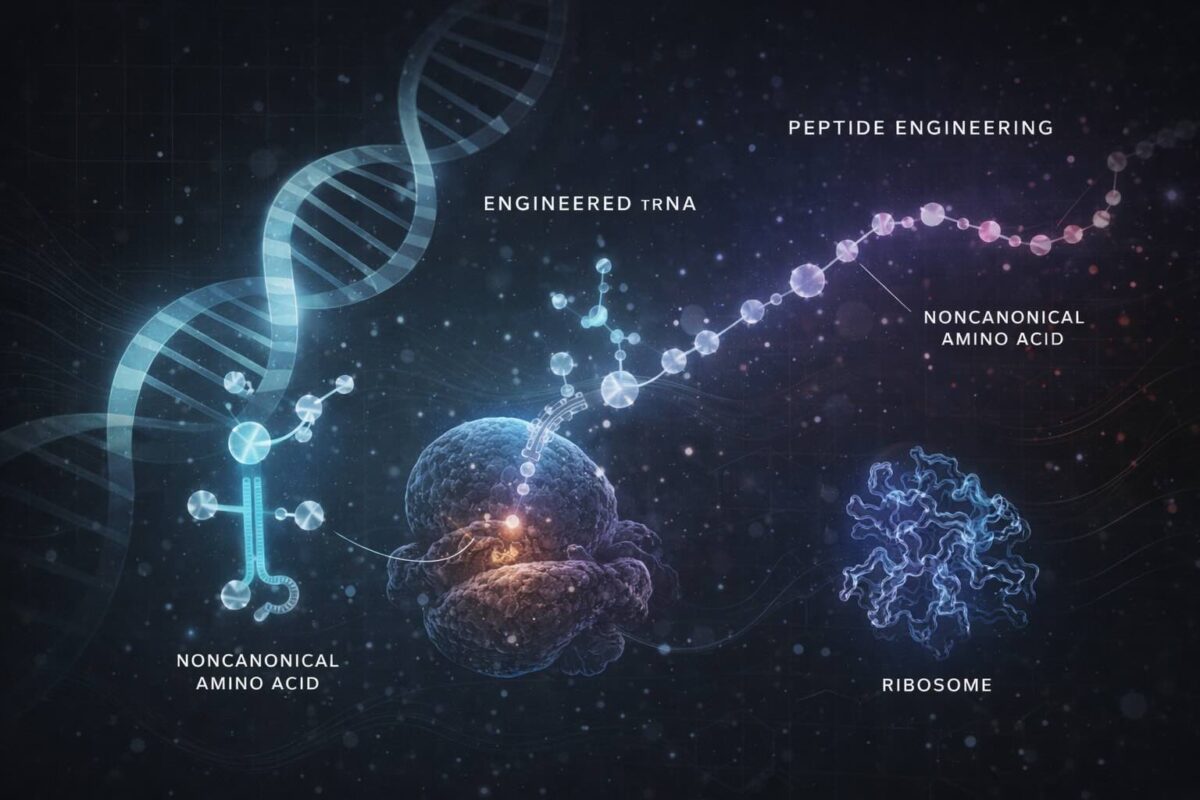

Expanding the Horizon of Peptide Therapeutics: How Engineered tRNAs Enable Ribosomal Incorporation of Noncanonical Amino Acids